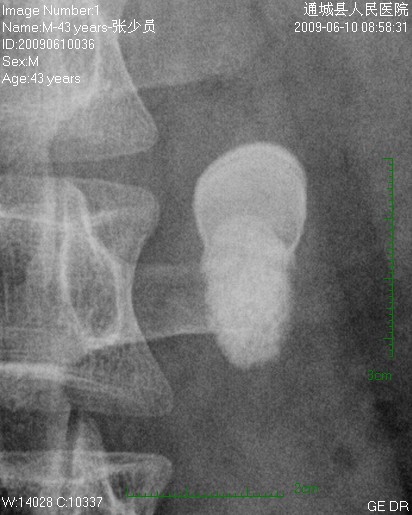

标题: CL1983:尿路结石

这颗石头长得怪,好象有顶帽子戴。

左侧输尿管结石并左肾积水